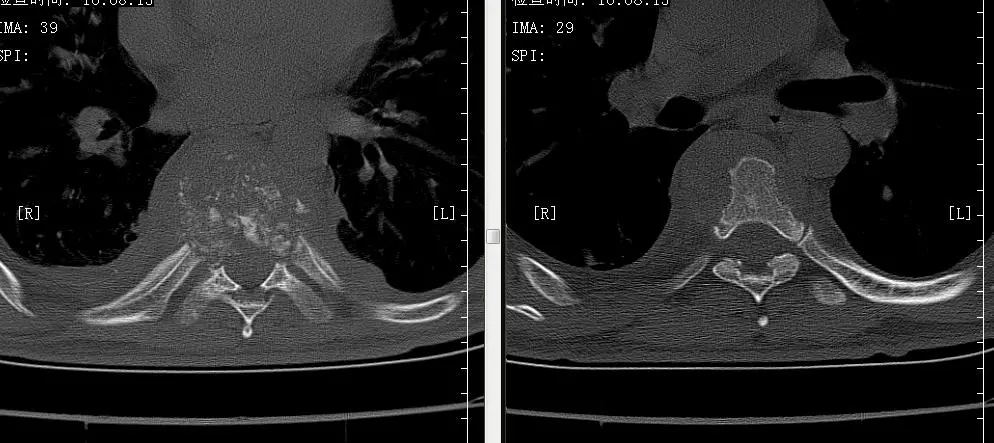

3床 胸9椎体结核